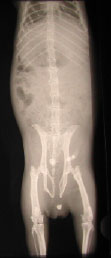

Stein in der Harnröhre

der herausmassierte Blasenstein

Das Meerschweinchen „Paula“ der Familie Linhart hat große Probleme, wir haben Steine in der Blase, im Harnleiter und in der Harnröhre festgestellt. Wir haben es stationär aufgenommen und zunächst den Stein aus der Harnröhre herausmassiert . Nun kann es wieder schmerzfrei Urin absetzen und wir haben etwas Zeit gewonnen, um das weitere Vorgehen mit den Besitzern zu besprechen.